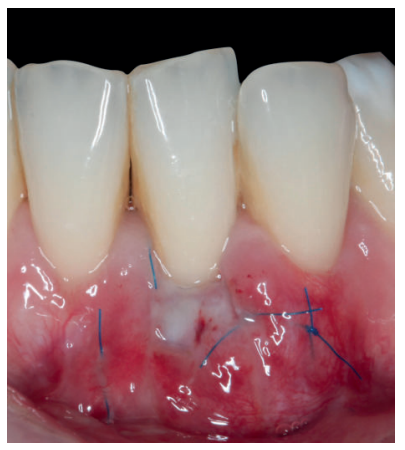

Una vez creado el lecho receptor, se procedió a la obtención de un ITC de la mucosa masticatoria palatina y a la sutura de dicho injerto mediante dos puntos colchoneros horizontales, uno situado en la parte mesial y otro en la parte distal del sobre. Para mayor adaptación y estabilización de las papilas se realizó un punto suspensorio cogiendo papila e ITC, mediante sutura de 6/0 no reabsorbible (Figura 3).

También, se realizó una sutura dentosuspendida para asegurar el injerto en posición apical, este punto se ancló en el periostio apical al injerto y suspendido alrededor de la cara lingual del diente con recesión mediante sutura de 5/0 reabsorbible. Se dejó cicatrizar por segunda intención en la base (zona de la vestibuloplastia).